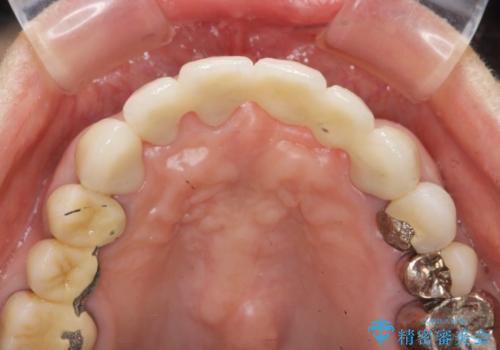

元々の噛み合わせが深く(ディープバイト)、転んで顎を強打したことで上顎前歯2本が根元から折れてしまい抜歯をしなければいけない状況となってしまいました。

抜歯後の見た目改善として深い咬合関係であることからインプラントは避け、ブリッジで補綴治療を行っていくこととしました。